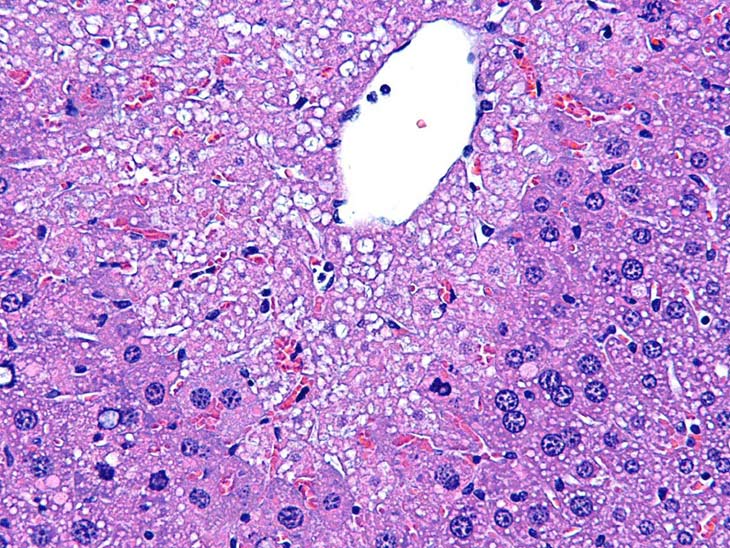

This is an example of centrilobular hepatocellular necrosis with associated hemorrhage sometimes referred to as hemorrhagic necrosis.

Marked centrilobular necrosis in a B6C3F1 male mouse chronically fed acetaminophen. Note depression of liver surface due to hepatocyte loss and pigment deposition. Areas of hemorrhage are often associated with the necrosis.